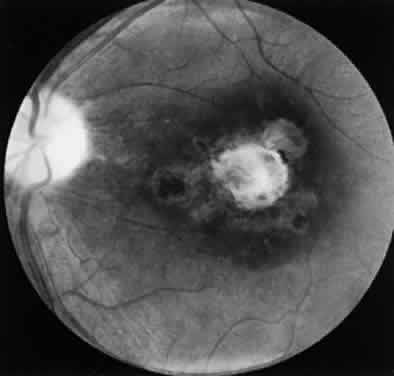

Bradyzoites are slowly metabolizing organisms found in cysts formed within the tissue of the infected host. The size of the Toxoplasma cyst varies, depending on the number of organisms that have multiplied within it. The cyst may reach more than 100 μm in diameter and may contain from 50 to 3000 organisms. The cyst wall is strongly argyrophilic and periodic acid-Schiff positive. It contains constituents that are derived from both the parasite and the host tissue. Constituent from the host tissue compose the outer part of the cyst, whereas those derived from the parasite are in the inner part of the cyst wall. Toxoplasmosis may be found in the inner layers of the retina after episodes of acute retinochoroiditis. The cyst may stay in the retinal tissue for years without showing any signs of invasiveness. Considering that the tissue cyst incorporates elements derived from the host into its outer wall, it is easily tolerated by the host, and no inflammatory reaction is seen around it (Fig. 2). It may remain for years in certain tissues, such as the eye or muscles, without provoking any inflammatory reactions. The bradyzoite inside the cyst derives its nutrition from the slow diffusion of substances through the cyst wall. The number of organisms increases within the cyst in the retina, and once the cyst wall breaks down by mechanical stretching, the bradyzoites escape, convert into tachyzoites, and invade contiguous cells. This process may lead to recurrence of retinitis. Certain immunologic mechanisms of the host may influence the organisms significantly. Immunosuppression coinciding with the rupture of the cyst and release of bradyzoites allows the organisms to become tachyzoites and proliferate in host tissue without restriction. The cyst of the Toxoplasma organism appears to be a defensive stage in its life cycle. The resistance of toxoplasmosis within chronically infected tissues of animals may lead to transmission of the disease by the ingestion of undercooked meat, including mutton, beef, pork, and chicken. Tissue cysts can develop within any organ and are commonly found in infected tissues of brain, eye, heart, skeletal muscles, and lymph nodes. Rupture of tissue cysts causes reactivation of the systemic toxoplasmosis in immune deficiency states, leading to dissemination of Toxoplasma organisms to other organs.